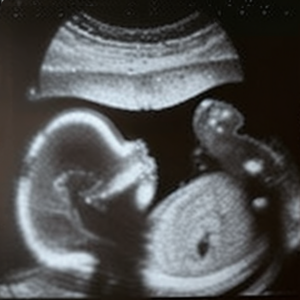

Schlagwort: Abtreibung